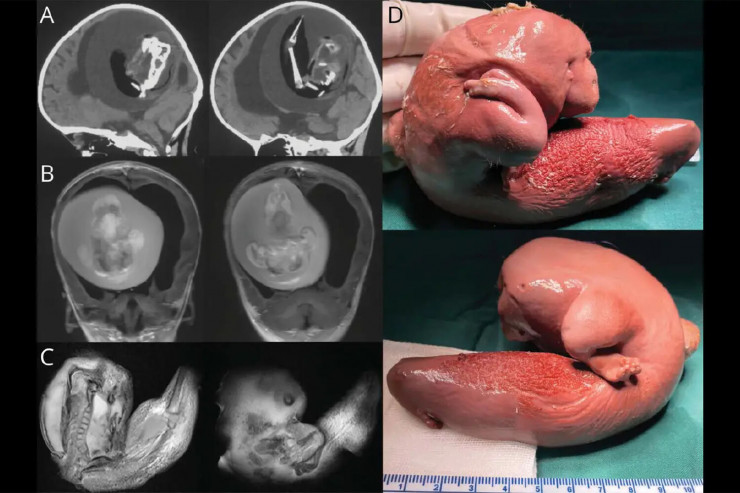

Плод близнеца извлекли из головы годовалой девочки в Китае

Хирурги из Китая удалили из мозга годовалой девочки плод ее близнеца, передает Tengrinews.kz со ссылкой на gazeta.ru.

Плод длиной около 10 сантиметров обнаружили в мозге девочки, когда родители отвезли ее в больницу из-за увеличения черепа и проблем с моторикой.

Врачи отметили, что у плода развились верхние конечности, кости и даже ногти. Это означает, что он, вероятно, продолжал расти в течение нескольких месяцев в теле сестры. Это было возможно, так как кровеносная система плода была соединена с системой кровообращения девочки.

Фото: Wolters Kluwer Health, Inc.

"Плод в плоде" - это медицинский термин, обозначающий редкое явление, при котором близнецы сливаются в утробе матери и один из них физически развивается внутри другого. Задокументировано всего около 200 случаев "плода в плоде". Их находили в области таза, рта, кишечника и даже мошонки. Случаев, связанных с черепом, насчитывается всего 18. Обычно их находили у младенцев, но несколько случаев были зарегистрированы среди взрослых. После операции по удалению больные обычно полностью выздоравливают.